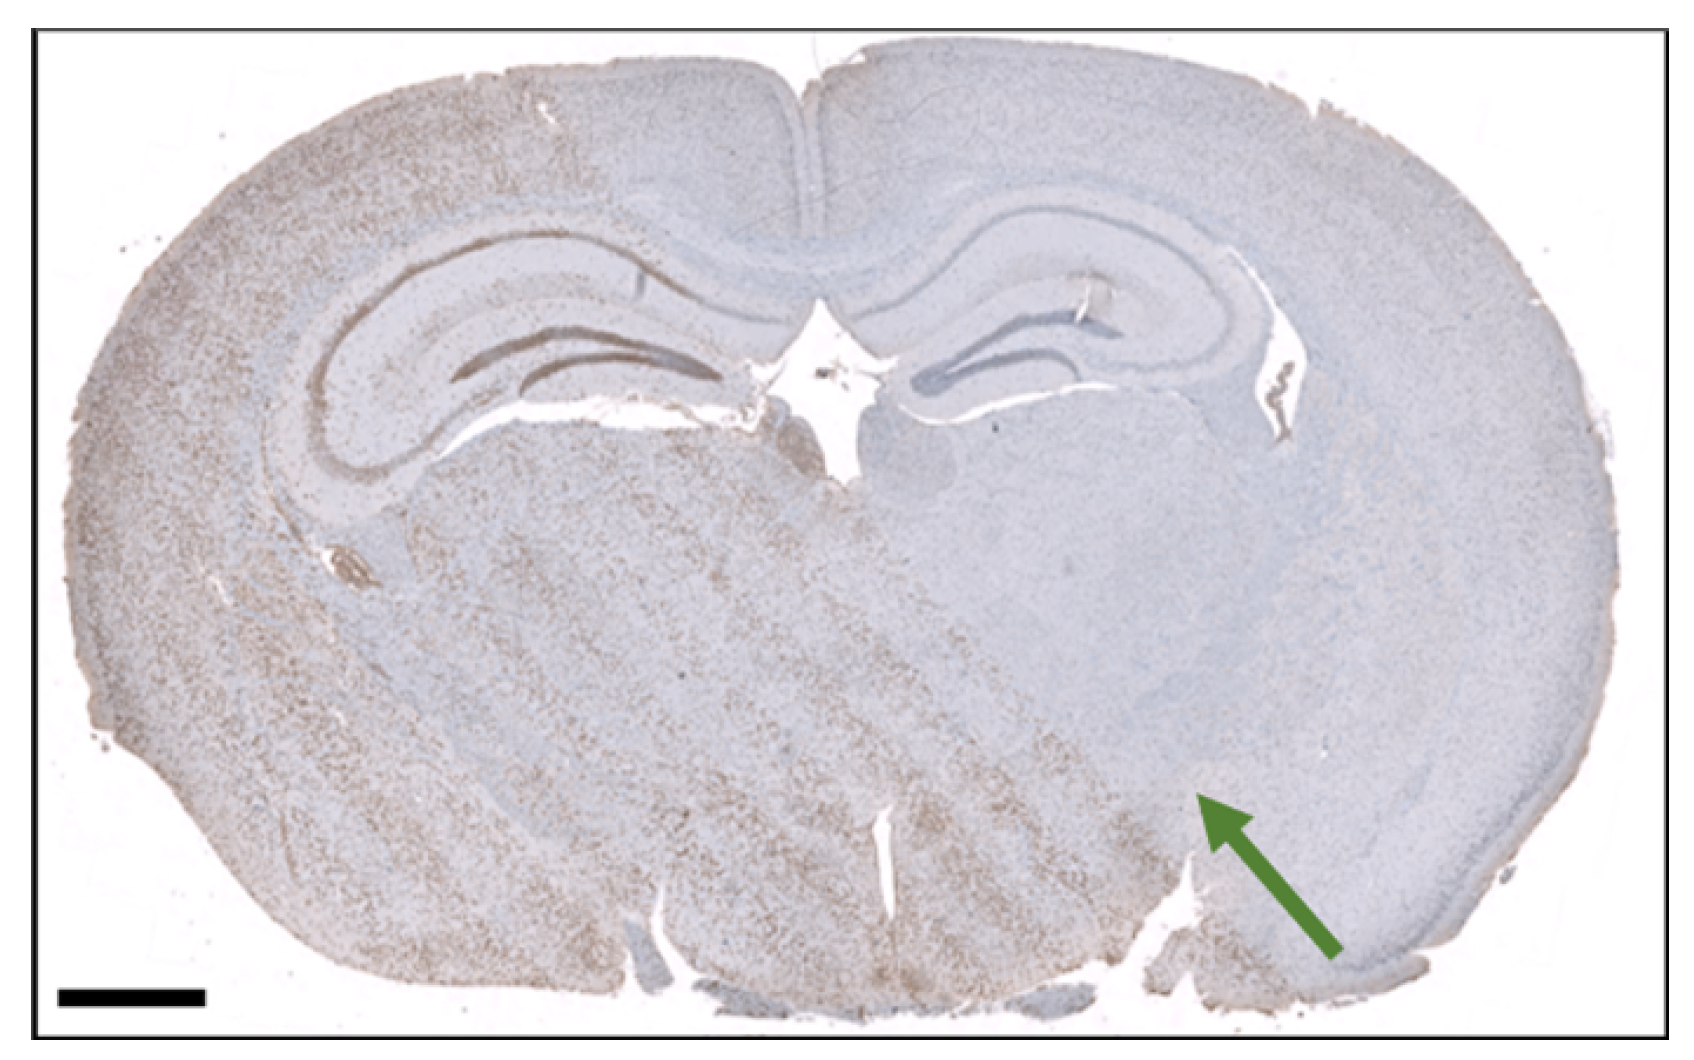

3.4. Histological Section of an Irradiated brain

4. Discussion